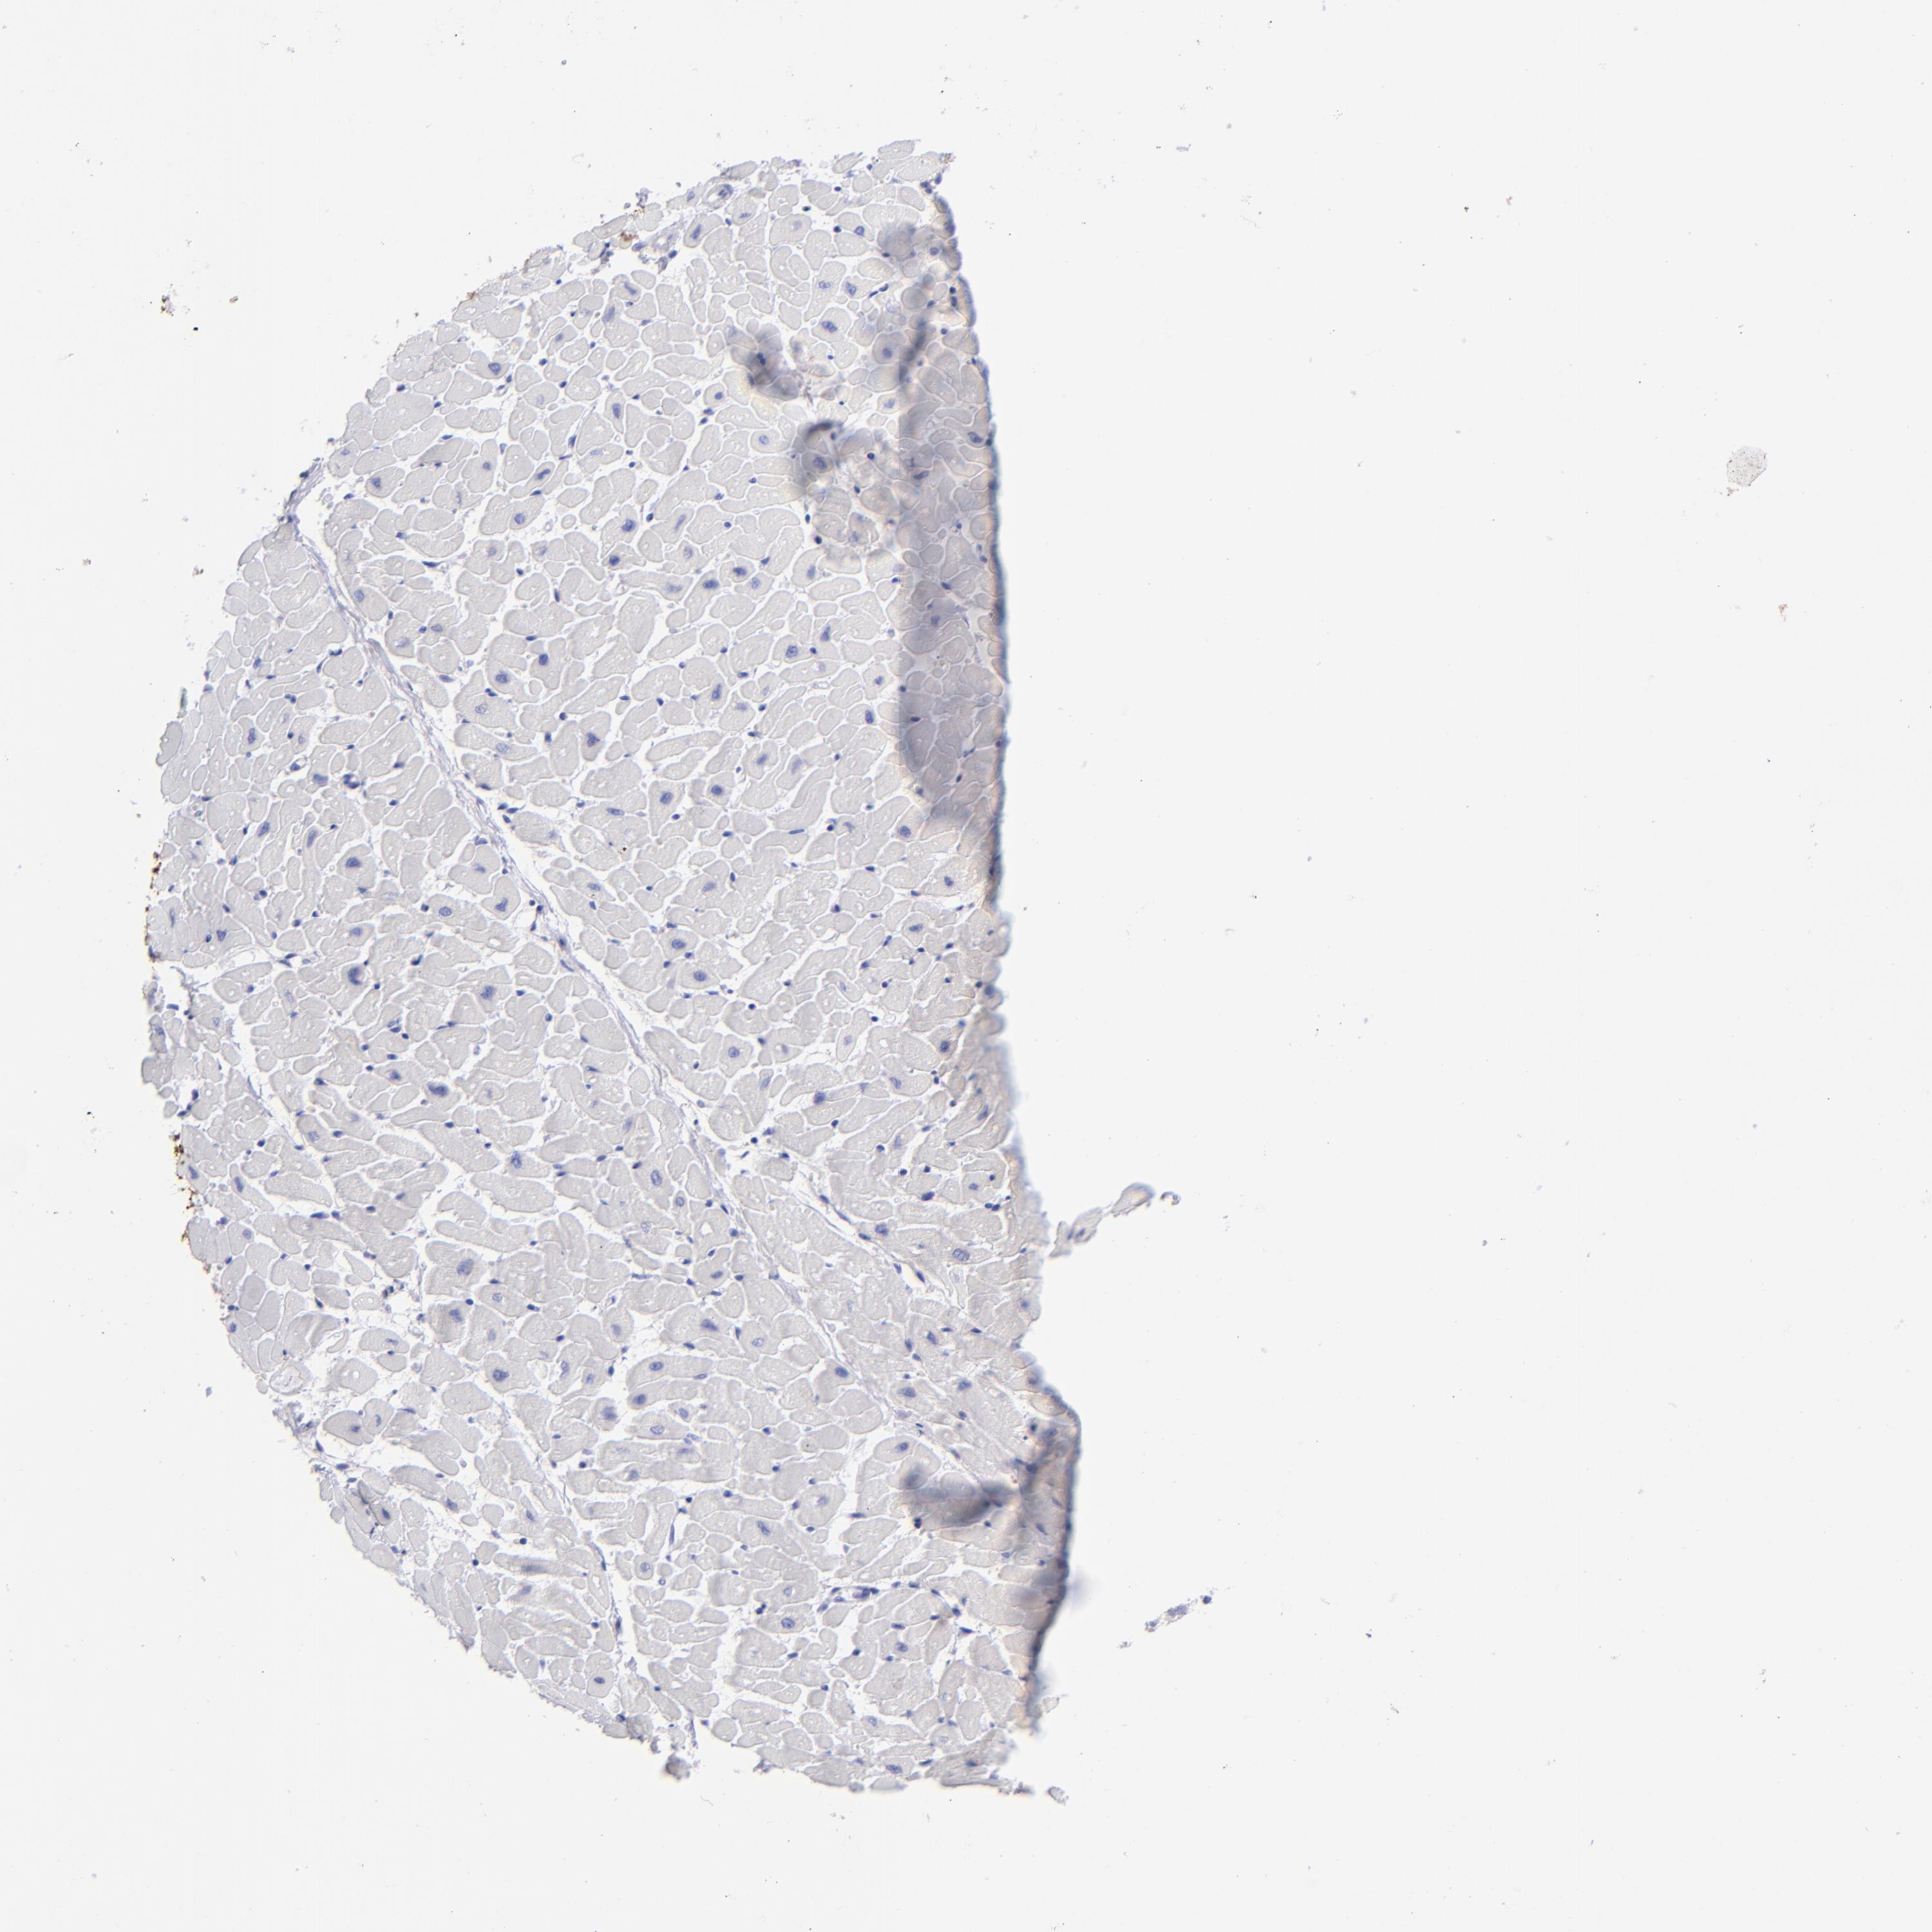

SLC1A3